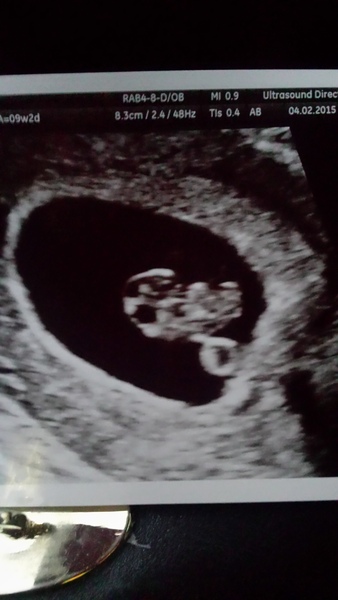

I realised the other day that although I have seen a HB and still feel pregnant (although not many symptoms - nipples like bullets, waves of nausea, tiredness) I can't seem to reconcile in my head that everything could be ok. I keep expecting something to go wrong, I think its because at this stage I am remembering my miscarriage and my ectopic pregnancies and not my 2 successful ones.

So I think all this worry is normal and there is nothing we can do to control this so just roll with it! And if you're anything like me, keep a countdown chart in your head until your next scan. Mines on the 14th as we're off on holiday on the 18th (long distance for 10 days) and I wanted some reassurance.